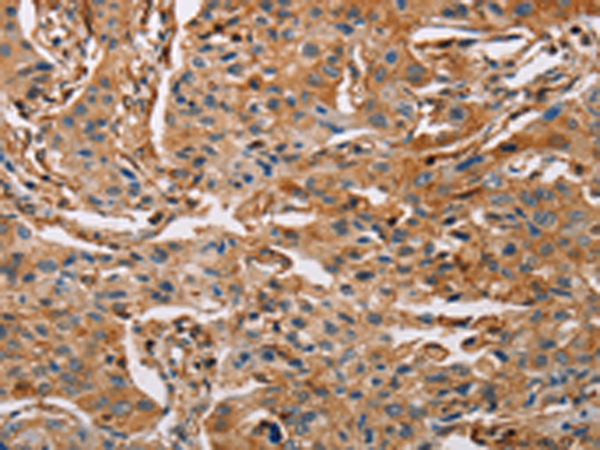

分类: 科研抗体货号: P07869别名: A3G; ARCD; ARP9; ARP-9; CEM15; CEM-15; MDS019; bK150C2.7; dJ494G10.1应用: WB,IHC反应种属: Human